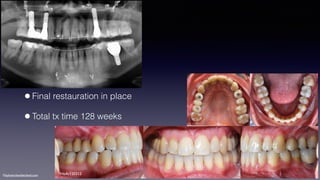

•Final restauration in place

•Total tx time 128 weeks

HeAr120312